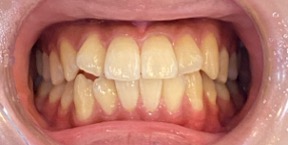

30歳女性のビフォーアフター

| 診断 | 叢生 |

| 治療方針 | 治療方針:インビザラインシステムにて主にIPR(歯と歯の間をわずかに削合してスペースを獲得する方法)を組み込んだ動的矯正治療を行い、叢生を改善後、保定を行う。 |

| 治療費 ※ | 96万5千円(診断、型取り、矯正中のメンテナンス、保定装置を含む料金) |

| 治療期間 | 1年8か月 |